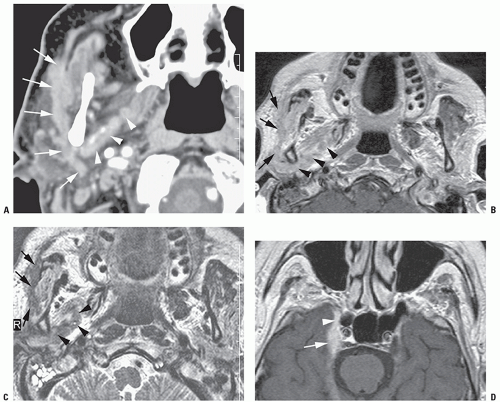

External Ear Disease

External Ear disease Source : www.slideshare.net